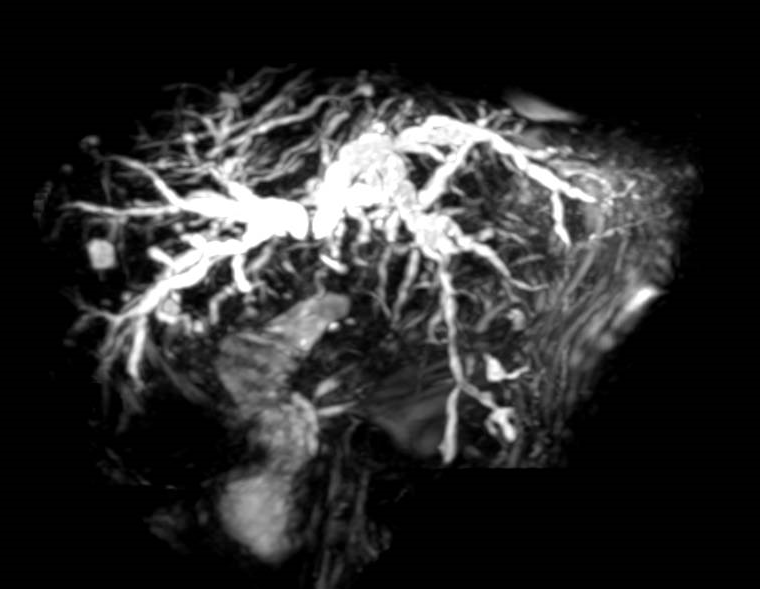

湖北日报客户端讯 近日,荆州一医消化内科团队成功为一位97岁超高龄、病情危重患者进行“经内镜逆行胰胆管造影术(ERCP)”,“免开刀”解除了胆管梗阻,老人术后恢复良好。此次手术打破了该院ERCP手术患者的最高年龄纪录。

仔细做完相关检查,消化内镜中心负责人张军发现,老人的肝内胆管扩张、肝门部位狭窄。原来,老人是胆管梗阻引起的梗阻性黄疸。

一切准备就绪,手术正式开始。在全麻下,张军带领ERCP团队,成功为陈爷爷置入了一枚金属胆管支架,使闭塞的胆管再次通畅。术后陈爷爷肝功能逐渐恢复,食欲以及精神明显好转。

据了解,ERCP现已成为诊治胆胰疾病的重要手段,是一种经人体自然腔道操作的微创手术,颠覆了传统开腹手术的治疗理念,部分情况下可替代创伤性较大的手术方式,简化了复杂而危险的治疗方法,可在明确诊断的同时进行治疗,具有简便、快速、高效、安全、对患者损伤小、并发症少、死亡率低等优点,能最大程度地满足人们提升生活质量、追求生命健康的需求。